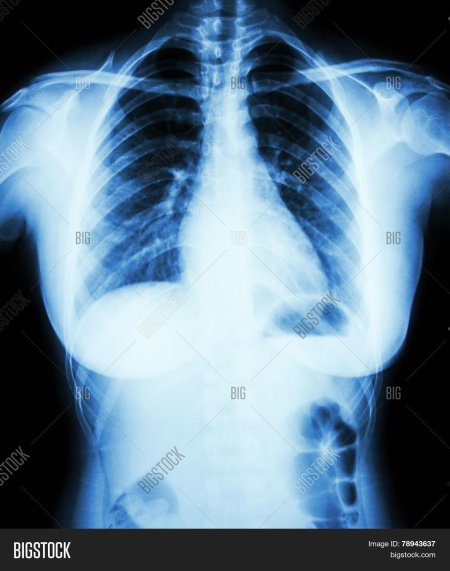

Рентгеновский эффект создает фантастические композиции в этих фотографиях девушки, чье тело становится прозрачным, демонстрируя скелет и внутренние органы. Она позирует в разных позах, ее силуэт светится загадочным свечением. Каждый кадр передает атмосферу научной фантастики и медицинского искусства. Ее кожа кажется полупрозрачной, позволяя увидеть кости и мышцы. Фотографии рассказывают о хрупкости человеческого тела и его внутренней красоте. Девушка то стоит в задумчивости, то делает грациозное движение. Эти иллюстрации вдохновляют на размышления о человеческой анатомии и уязвимости. Каждая картинка - это момент прозрения, когда внешнее уступает место внутреннему. Девушка воплощает образ современной Медузы, сочетающей красоту и загадочность.

Сквозь материю: тайны анатомии